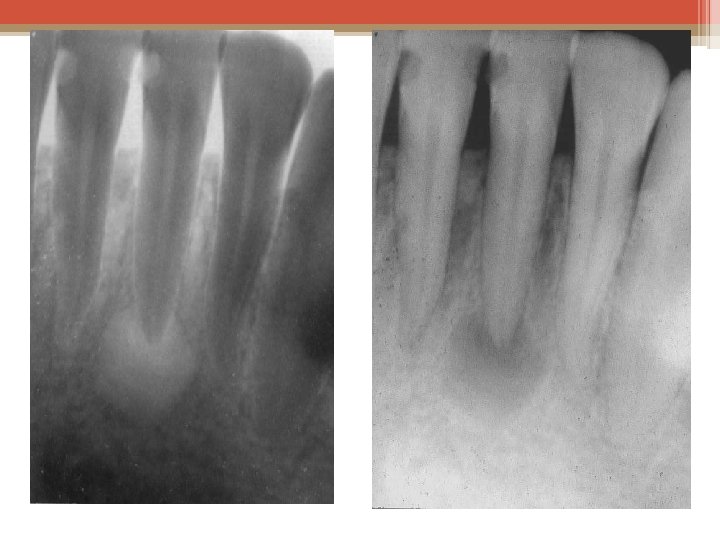

Radiography is used in many types of examinations and procedures where a record of a static image is desired. Some examples include ▫ Dental examination ▫ Verification of correct placement of surgical markers prior to invasive procedures ▫ Mammography ▫ Orthopedic evaluations ▫ Spot film or recording during fluoroscopy ▫ Chiropractic examinations

X-Ray Imaging • X-rays are waves that have a relatively high frequency along the electromagnetic spectrum. They are absorbed or transmitted by different body tissues in varying amounts, producing different shades of black and white on an x-ray image. X-Ray Imaging The basic type of x-ray imaging is plain radiography. This involves an x-ray machine aimed at the patient's body with a recording plate positioned behind the region of interest. Once the machine delivers its radiation, the image is captured on the plate. This allows a physician to assess the bones for fractures, abdomen In general, bone appears white, soft tissue appears the gray, and air for bowelblack. obstruction, and the breasts for signs of cancer appears (mammography), among other applications.